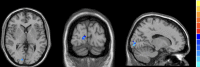

Methods: Thirty-six active TAO patients with active phase and 39 healthy controls (HCs) were enrolled in this study. All participants underwent resting-state functional magnetic resonance imaging (rs-fMRI), neuropsychological tests, and ophthalmological examinations. The rs-fMRI-based fractional low-frequency fluctuation amplitude (fALFF) analysis methods were used to assess spontaneous brain activity in both groups. The structure (peripapillary retinal nerve fiber layer, pRNFL) and microvascular indices (the optic nerve head (ONH) whole image vessel density, ONH-wiVD, and peripapillary vessel density) were analyzed through optical coherence tomographic angiography imaging. The relationship between abnormal spontaneous brain activity and ophthalmological indices was analyzed using the Spearman's rank correlation analysis.

Results: Compared with HCs, active TAO patients had increased fALFF in the right inferior temporal gyrus (R.ITG) and left posterior cingulate gyrus (L.PCC), but decreased fALFF in the right calcarine (R.CAL). The fALFF values in L.PCC were positively correlated with peripapillary vessel density, whereas fALFF values in R.CAL were negatively related to peripapillary vessel density.